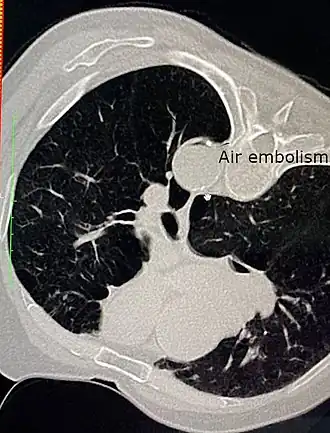

Га́зовая эмболи́я — заболевание, возникающее вследствие прорыва стенок альвеол с капиллярами, что приводит к выносу воздушных пузырьков в кровеносное русло. Кровь приносит их в сердце, откуда они попадают в артерии большого круга кровообращения и достигают жизненно важных органов, препятствуя их нормальному кровоснабжению и повреждая стенки кровеносных сосудов.

Газовая эмболия является наиболее серьёзной формой баротравмы лёгких. Она характеризуется повреждением лёгких и пульмонарных капилляров с последующим проникновением пузырьков газа в кровеносное русло.